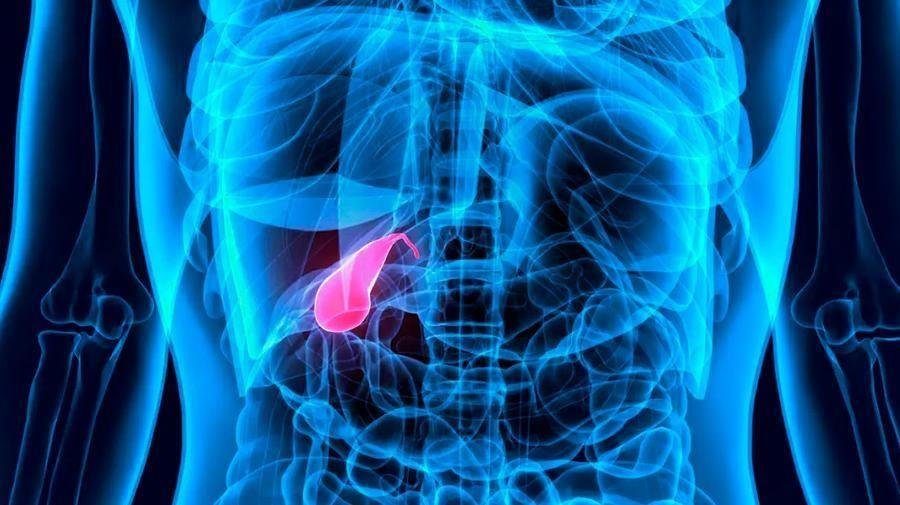

Λαπαροσκοπική χολοκυστεκτομή

Λαπαροσκοπική χολοκυστεκτομή

Ο Γενικός Χειρουργός Λιάγκος Γεώργιος MD PhD εκτελεί τις επεμβάσεις Λαπαροσκοπικά, Ενδοσκοπικά, Ανοιχτά Ελάχιστα Επεμβατικά και με Laser. Η θεραπεία εξατομικεύεται σε κάθε ασθενή ανάλογα με τις ανάγκες του. Αναλαμβάνει περιπτώσεις όπως κήλες και κοιλιοκήλες (αντιμετώπιση βουβωνοκήλης, αντιμετώπιση ομφαλοκήλης, θεραπεία επιγαστρικής κήλης, κήλη των αθλητών (Σύνδρομο κοιλιακών προσαγωγών), αντιμετώπιση μετεγχειρητικής κήλης, θεραπεία Μηροκήλης), πέτρες στη χοληδόχο κύστη, λαπαροσκοπική χολοκυστεκτομή, αντιμετώπιση Κύστη Κόκκυγος με λέιζερ (laser), παθήσεις πρωκτού, χειρουργική laser σύγχρονων κυκλικών ινών (αιμορροΐδες αντιμετώπιση, θεραπεία αιμορροϊδων με laser (LHP), αφαίρεση αιμορροΐδων με υπερήχους (HALL-RAR), χωρίς Χειρουργείο με ελαστικούς δακτυλίους (Τεχνική BARON-RBL), θεραπεία ραγάδας πρωκτού (Ραγάδα δακτυλίου), θεραπεία περιεδρικού συριγγίου, θεραπεία περιεδρικού αποστήματος, κονδυλώματα πρωκτού Θεραπεία, δερματικό ράκος (Skin tag) εκτομή, αντιμετώπιση Kνησμού, καρκίνος πρωκτού θεραπεία), παθήσεις Δέρματος, χειρουργική με laser CO2, αφαίρεση μορφωμάτων δέρματος - βιοψίες, αφαίρεση ελιάς (Σπίλου), σμηγματογόνος κύστης θεραπεία, αφαίρεση λιπώματος, είσφρυση όνυχος χειρουργείο, καρκίνος δέρματος θεραπεία, οξεία σκωληκοειδίτιδα, παθήσεις Λεπτού και Παχέος Εντέρου, ειλεός λεπτού εντέρου, εκκολπωμάτωση (Εκκολπωματίτιδα) σιγμοειδούς, καρκίνος παχέος εντέου, κολοστομίες, port χημειοθεραπείας κ.α. εξυπηρετώντας Παγκράτι και γύρω περιοχές.